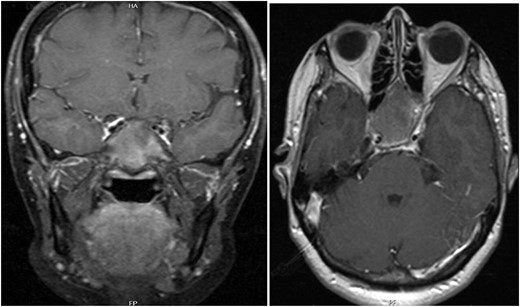

A 56-year-old female presented with a 1-year history of intermittent headaches, which had been increasing in severity and intensity over the last 2 months. The headache was mainly in the right parietal region, throbbing in nature and did not display diurnal variation. The severity of the headache was stated as 7–8 degrees on the Numerical Rating Pain Scale (NRPS; [6]). The pain was partially relieved with analgesia (acetominophen and ibuprofen). She also complained of mild right nasal congestion and intermittent mild otalgia. Physical examination was normal apart from nasal septal deviation. Computed tomography (CT) of the paranasal sinuses showed expansion of the sphenoid bone demonstrating diffuse ground-glass matrix and sclerosis obliterating the sphenoid sinus cavity (Fig. 1). Magnetic resonance imaging (MRI) was highly suggestive of fibrous dysplasia of the sphenoid bone, which appeared as expanded mass with dark T2 signal and T1 hypointense signal (Figs 2 and 3). Near-total excisional biopsy was performed using endoscopic transeptal approach to sphenoid sinuses. Histopathological examination of several pieces of greyish tan and brown bony tissue measuring 3.5 × 2.5 × 1.7 cm. showed branching irregular trabeculae of woven bone with intervening hypocellular fibrous stroma, consistent with a diagnosis of FD (Fig. 4). The patient’s headaches improved greatly following surgery. Two years post-op she reports infrequent headache with a severity of 2 on NRPS.

T1 axial and coronal post-contrast images show some heterogeneous enhancement compared to pre contrast images.